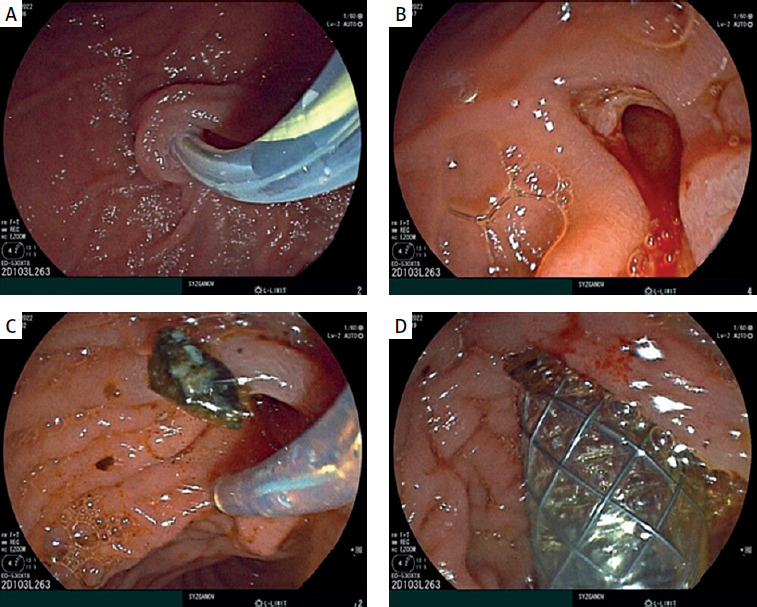

On 13th December 2022: During the endoscopy, the major duodenal papilla (MDP) was not enlarged. The common bile duct (CBD) was catheterized: the proximal part measured up to 1.0 cm in diameter, while the middle and lower thirds were cystically dilated to 2.5–3.0 cm, forming two cavities. Two shadows, measuring 1.1–1.3 cm in diameter, were observed in the lumen of the CBD in the distal part (Figure 3). Endoscopic papillosphincterotomy (EPST) was performed up to 0.7 cm with additional balloon dilation to 1.1 cm. The stones were extracted.

Figure 3

Fistulography during ERCP: visualization of the catheter in the common bile duct (choledochus)

During the procedure, subcutaneous emphysema of the chest, neck, and face was identified, suggesting a possible rupture of the choledochal cyst wall and the entry of air from the abdominal cavity into the mediastinum. To close the rupture of the choledochal cyst, it was decided to place an endobiliary stent. A metallic fully covered endobiliary stent, 6.0 cm in length, was placed in the CBD. After the stent placement, bile began to flow through the stent (Figure 4). After the placement of the endobiliary stent, no further progression of the subcutaneous emphysema was noted.

Figure 4

A – Catheterization of the common bile duct with a papillotome over a guidewire. B – Endoscopic papillosphincterotomy up to 0.7 cm with additional balloon dilation. C – Choledocholithotripsy. D – Insertion of a self-expanding metal stent